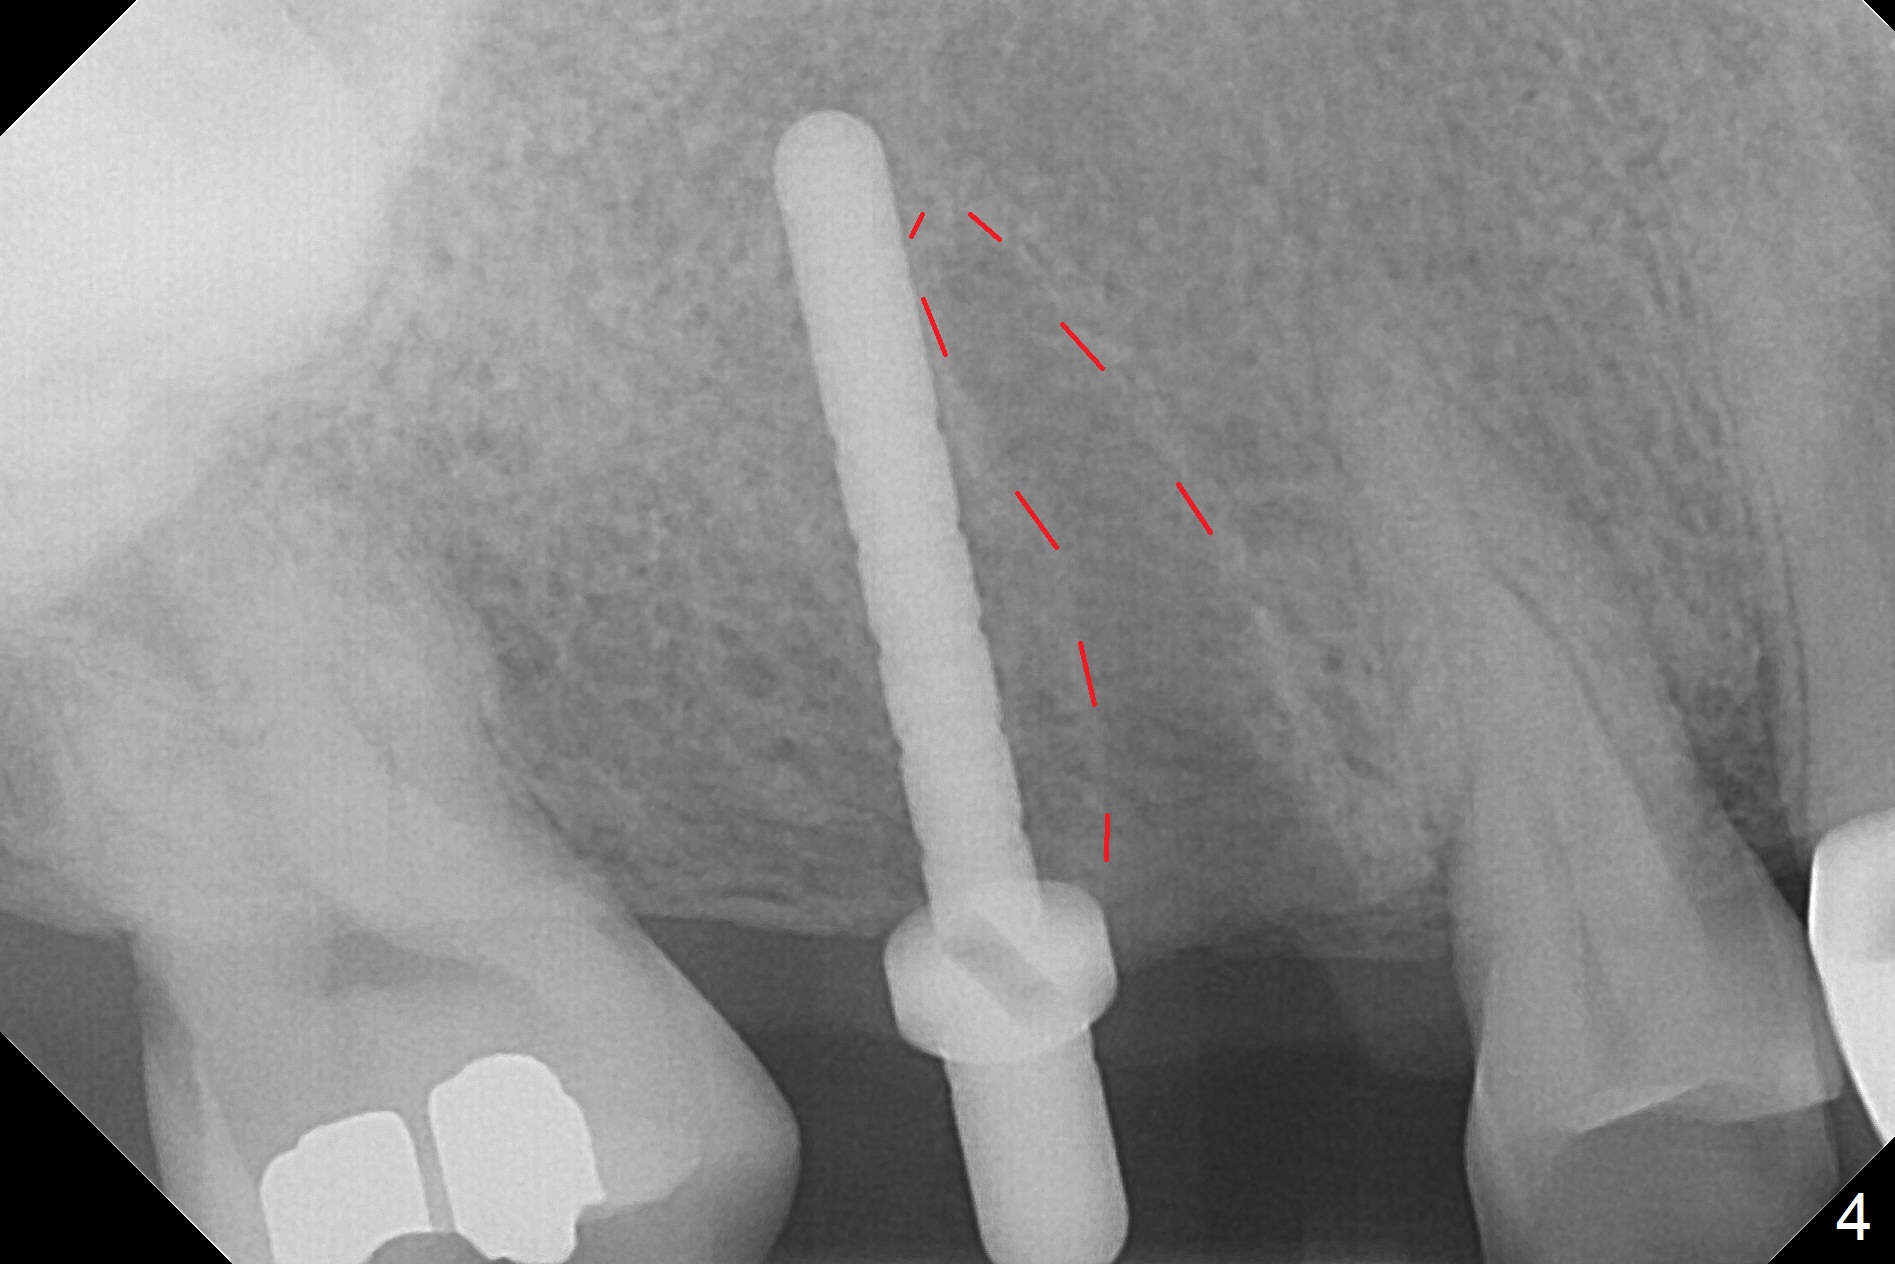

The palatal cusp of the affected 2nd premolar is apparently rotated distal (Fig.1). It is more obvious for the socket (Fig.2): the palatal (P) portion of the socket is more distal than the buccal (B) one. When the gauze is removed (Fig.3), Lindamann bur is used to remove the disto(D)palatal bone of the socket (data not shown), followed by starter drill in the DP wall obliquely (Fig.3'). Once the drill enters the bone for 1-2 mm, the bur is straightened and pushed slightly distal (Fig.3''). Fig.4 shows a parallel pin distal (overcorrect) to the original socket (Fig.4 red dashed line). Sequential osteotomy is conducted until 3.8x13 mm drill for 18 mm (Fig.5): note the 2 steps of the osteotomy (red lines). Since the apical portion of the osteotomy is larger than the drill, a larger implant than expected (5x16 mm) is placed. The implant ends up in the middle of the edentulous area (due to the stepped osteotomy; Fig.6-9; >60 Ncm). Vera allograft is placed (Fig.7-9 *) prior to and after placement of a 6.5x4(3) mm abutment (Fig.8-10). The remaining socket opening is sealed with a piece of Collagen plug (Fig.10 *). The socket is then closed by an immediate provisional (Fig.11 P). The abutment is retightened 2 months postop (Fig.12,13). The crown is cemented 4.5 months postop. Panoramic X-ray and CT are taken nearly 7 months post cementation (Fig.14,15) when the patient is ready for #30 implant guide preparation.